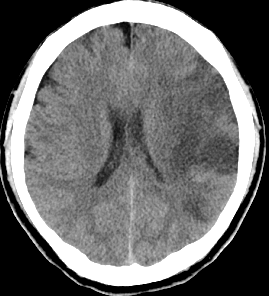

くも膜下出血

脳を包んでいるくも膜という薄い膜と脳の間に動脈が走っています。その動脈の壁に動脈瘤という膨らみが出来て、それが破れて起きるのがくも膜下出血です。この病気を起こす危険因子として高血圧、飲酒、喫煙が挙げられます。突然の激烈な頭痛で発症するのが特徴で、突然後ろから後頭部をバットで殴られたような痛みと表現されることもしばしばです。痛みの程度は出血量と関係しますので少量のくも膜下出血では頭痛の程度はそれほど強いものにはならないこともあります。頭部CTにより診断はつきますが、出血が少ない場合、見逃されることもありますのでぜひ専門医のいる病院をすぐ受診して検査を受けてください。破裂した脳動脈瘤を放置しておくとまず間違いなく再出血します。そのため再破裂、再出血予防の処置が必要となります。しかしながら昏睡状態やきわめて全身状態の悪いときには残念ながら手術治療のできない場合もあります。

くも膜下出血のCT

【くも膜下出血のCT】

Apoplexy 14

【脳動脈瘤;矢印の部位】